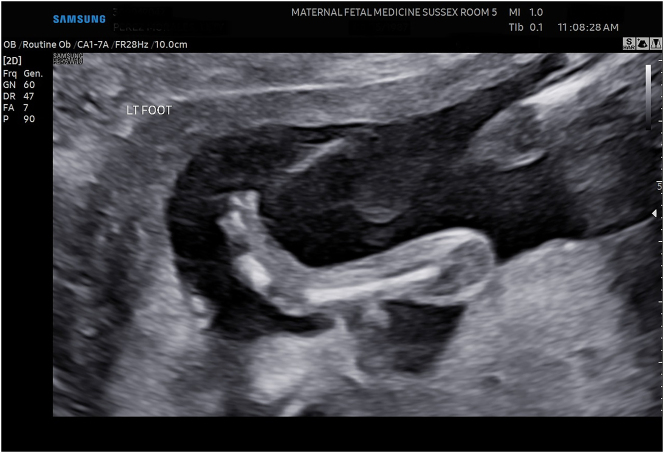

Case presentation: We present two cases of LCCS2, a rare autosomal recessive disorder in the arthrogryposis multiplex spectrum of syndromes whose sine qua non feature is the presence of nonobstructive, neurogenic megacystis. The prenatal diagnosis of this syndrome has not been previously reported. This syndrome has been previously studied in detail in an Israeli-Bedouin kindred but it has not been reported in the Americas.

Abstract Image